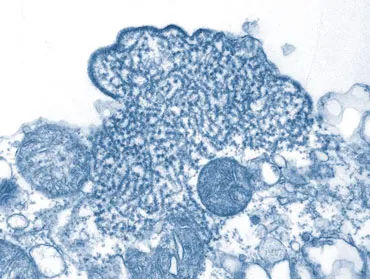

How does the virus cause infection?

Nipah and its viral cousin Hendra latch onto a proteins called ephrin-B2 and ephrin-B3 on the surface of nerve cells and the endothelial cells lining blood and lymph vessels, researchers have found. Nipah can also invade lung and kidney cells.

Virologists who have studied Nipah’s behavior in animals think that in humans, it initially targets the respiratory system before spreading to the nervous system and brain. Most patients who die succumb to an inflammation of blood vessels and a swelling of the brain that occurs in the later stages of the disease.